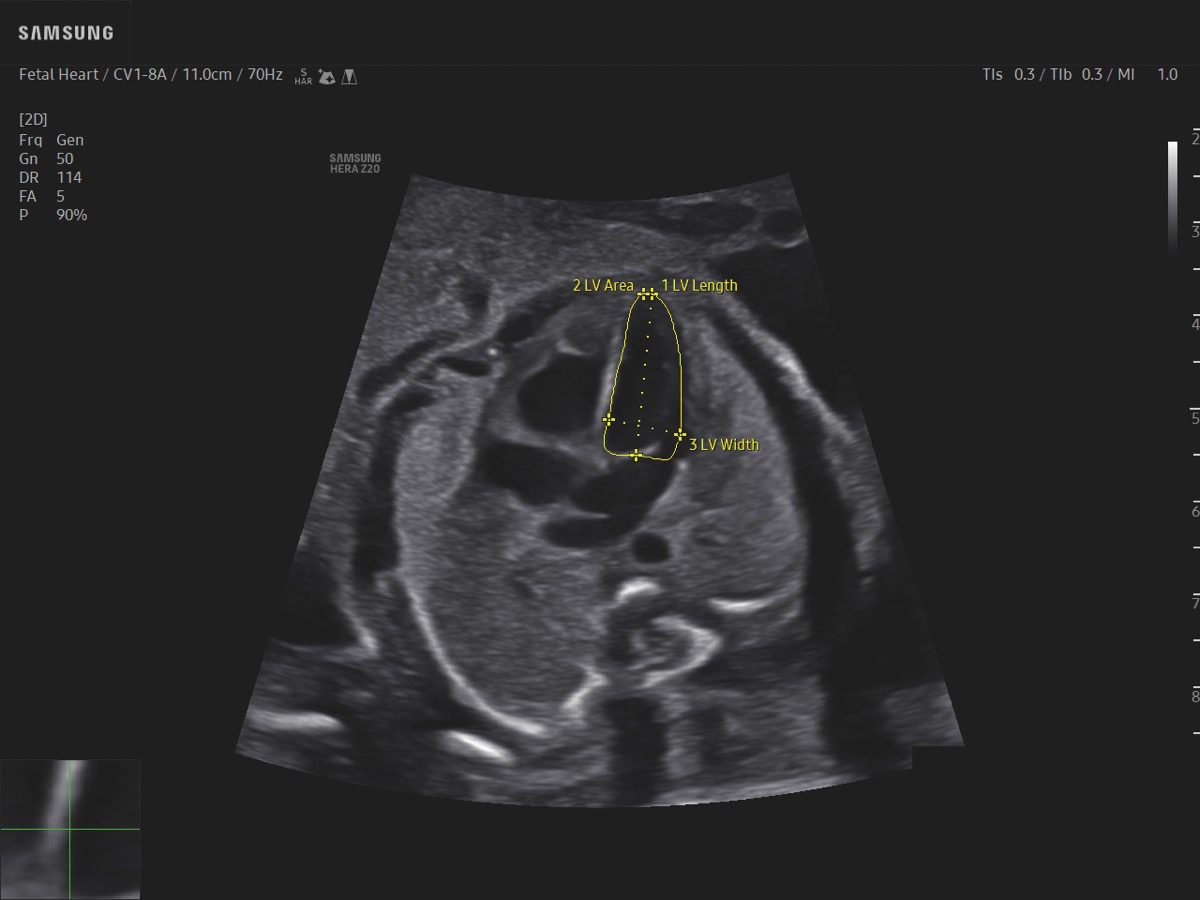

Procedural Services

Comprehensive, advanced and expert MFM care for high-risk pregnancies

- Fetal anomalies